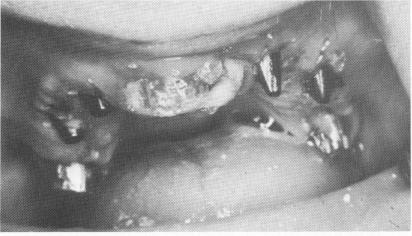

Fig. 11-129. In order to finish the prosthesis as rapidly as possible, the copings were fitted at this very same visit.

2 Copings fitted over maxillary implants